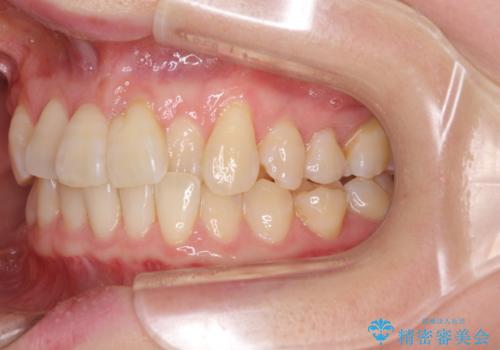

前歯のクロスバイト インビザライン矯正で改善

- むし歯治療を契機に、長年気にしていた前歯のクロスバイトの改善を希望された患者様です。

汚れが溜まりやすく、歯ぎしりがうまくできないため、インビザラインを用いて矯正治療を行うこととしました。

インビザラインによる前歯のクロスバイトの改善は、治療期間中に前歯でしか咬めない時期が続いたり、歯肉退縮や歯髄壊死のリスクが高まったりと、治療中にトラブルを抱えることがあります。

特に上顎側切歯(真ん中から2番目の歯)が舌側に引っ込んでいるケースは、インビザラインでは改善しきれないことがあると言われています。